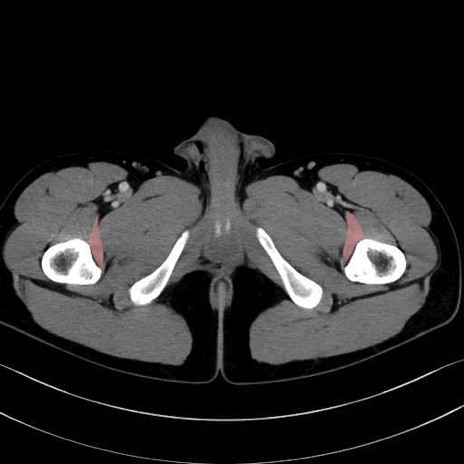

内閉鎖筋 (Obturator internus)

外閉鎖筋 (Obturator externus)